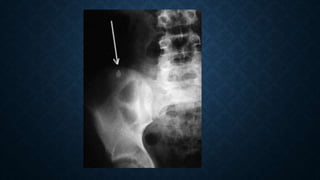

ESTUDIOS DE IMAGEN

• Radiografía simple de abdomen

Patrón anormal de gas intestinal, presencia de fecalito

ESTUDIOS DE IMAGEN •Radiografía simple de abdomen Patrón anormal de gas intestinal, presencia de fecalito Schwartz. Principios de cirugía. MC Graw Hill. 9 ed. 2011